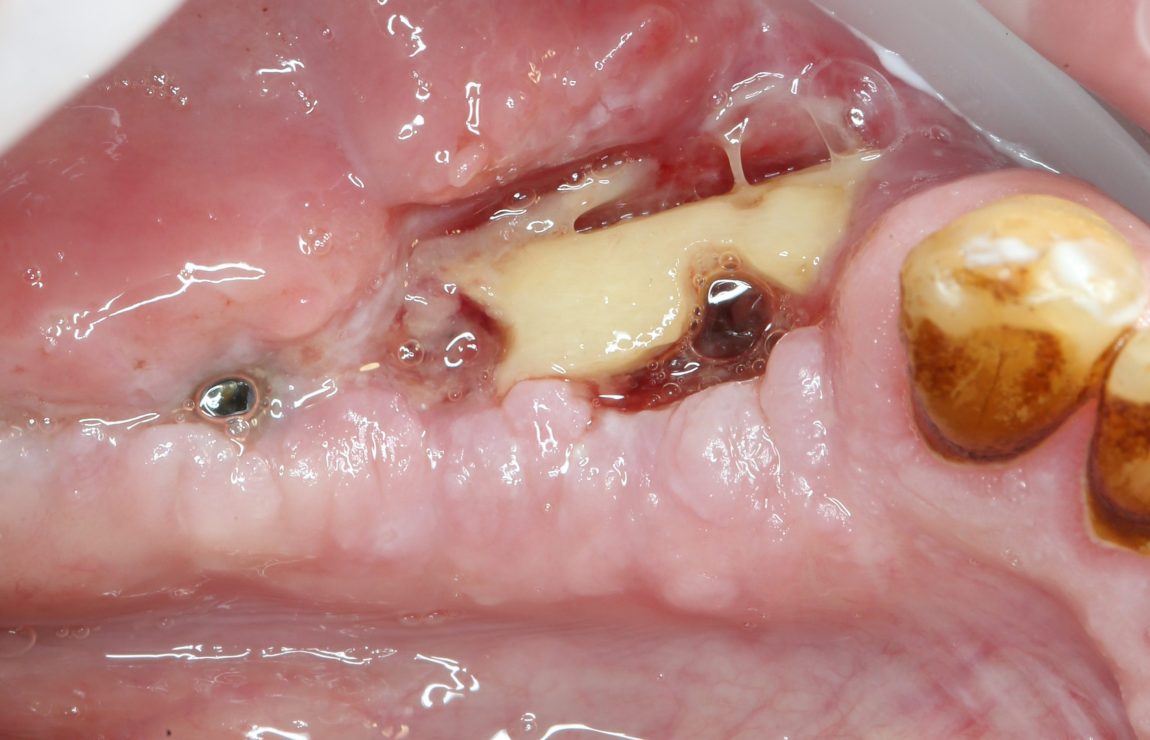

Поговорим о неудачах. Нам, в стоматологическом центре CLINIC IN, иногда приходится иметь дело с неудачами. Редко — со своими (из более, чем трёхсот операций остеопластики в прошлом году, пришлось переделать семь), гораздо чаще — с плохими негодными результатами операций наращивания кости, проведённых в других клиниках.

Как правило, в случае неудачи, при повторном вмешательстве мы кардинально меняем методику остеопластики. Если до этого проводили НКР, то при переделке используем остеотомию или блоки. Если неудачной была остеотомия — то работаем по методу направленной костной регенерации или проводим аутотрансплантацию крупных костных фрагментов. Подробнее о различных методах остеопластики можно почитать здесь>>